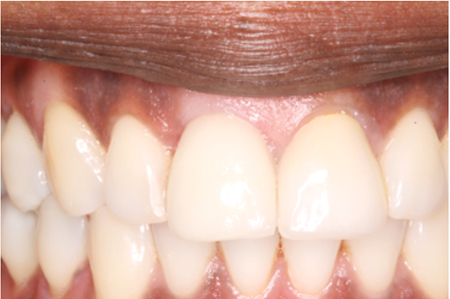

Gingival Grafting: A Novel Approach To Single Stage Augmentation For Root Coverage

Abstract The existence and preservation of attached keratinized gingiva around natural teeth and dental implants plays an important role in periodontal1 and peri-implant health.46,47 This paper describes a novel surgical technique that addresses multiple adjacent Miller class II and III recession defects5 in a predictable one staged surgical procedure. The goal of treatment is to improve esthetic outcomes, gain clinical attachment … Read more